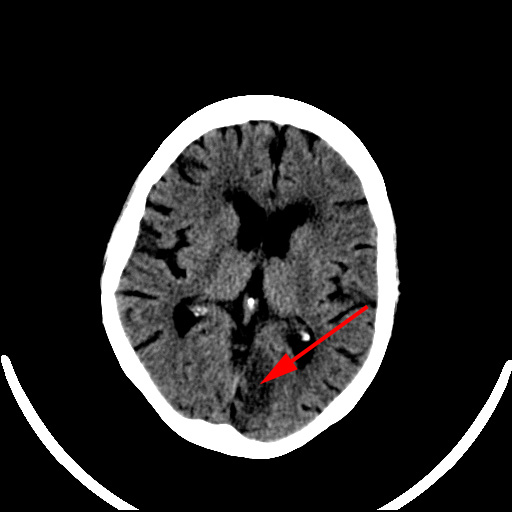

CT-skanning af cerebrum viser et ældre infarkt (rød pil) i den venstre occipitallap.